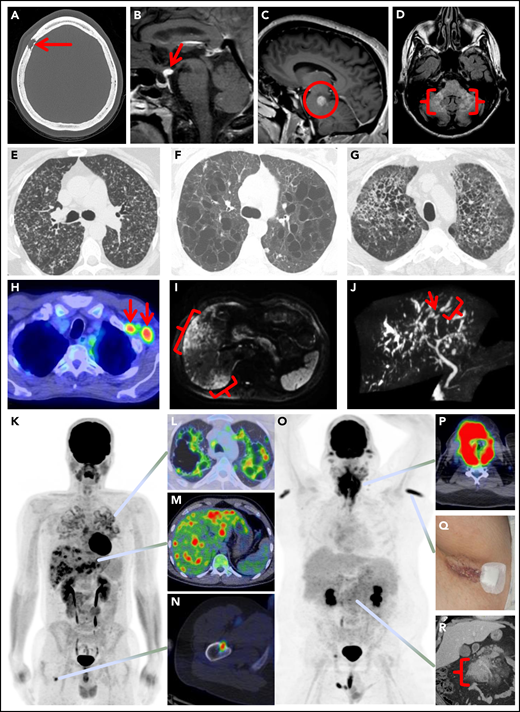

LCH has diverse manifestations in adults, with varying frequencies of disease sites based mostly upon institutional retrospective series (Figure 1; Table 3; supplemental Appendix 2).6,15,33,37-81 Clinicians should be familiar with the clinical and radiographic features of LCH and attempt to pursue comprehensive evaluation at baseline given the implications for diagnosis and management of the disease.

Spectrum of manifestations of LCH in adults. (A) Axial computed tomography (CT) of the calvarium demonstrating a lytic lesion with a beveled edge (arrow). (B) Sagittal pituitary T2 weighted fluid-attenuated inversion recovery (FLAIR) magnetic resonance imaging (MRI) highlighting a hypothalamic lesion with increased FLAIR signal (arrow). (C) Sagittal T1 weighted contrast-enhanced brain MRI demonstrating an enhancing posterior midbrain/pons lesion (circle). (D) Axial brain MRI with a neurodegenerative pattern of T2 signal abnormality throughout the bilateral cerebellar peduncles (brackets). (E-G) Axial CT of the mid to upper chest demonstrating variable appearances of pulmonary LCH to include the most common nodulocystic pattern ground-glass nodules and cysts (E), a cystic-predominant pattern with larger irregular cysts and a few scattered nodules (F), and more confluent combined cystic and nodular disease with architectural distortion consistent with elements of fibrosis (G). (H) Axial fused 18F-fluorodeoxyglucose positron emission tomography CT (FDG PET/CT) of the chest demonstrating 2 FDG avid left axillary lymph nodes (arrows). (I) Diffusion-weighted MRI of the liver demonstrating an infiltrative pattern of increased signal throughout the right hepatic lobe (brackets). (J) Magnetic resonance cholangiopancreatography demonstrating multifocal stricturing (arrow) and dilatation (bracket) of the intrahepatic ducts. (K) Maximum intensity projection FDG PET/CT demonstrating FDG avid advanced pulmonary disease (L), multifocal FDG avid hepatic disease (M), and an FDG avid lytic right femur lesion (N). (O) MIP FDG PET/CT demonstrating an infiltrative FDG avid laryngeal mass (P), bilateral axillary dermal lesions with associated left axillary photograph (Q), and a mildly FDG avid mesenteric mass highlighted with a bracket (R).